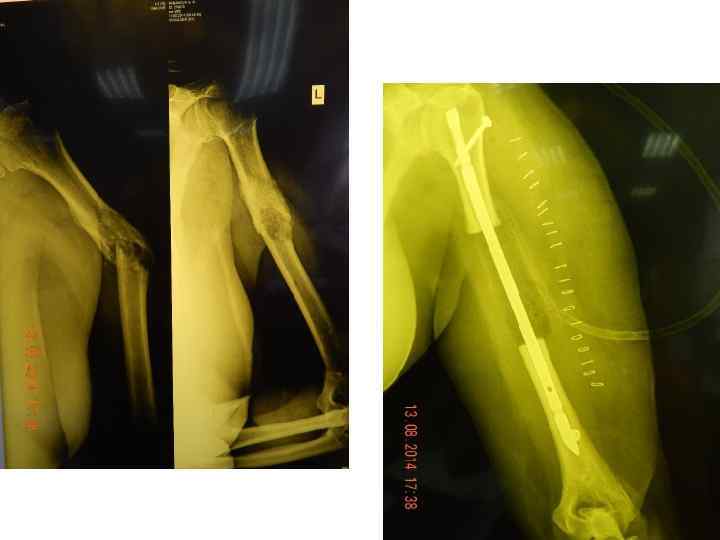

Ортопедическая хирургия реконструкция вертлужной впадины • Напечатанные 3 D модели используются для анализа переломов и определения точного местонахождения и траектории винтов выравнивания и пластин фиксации.